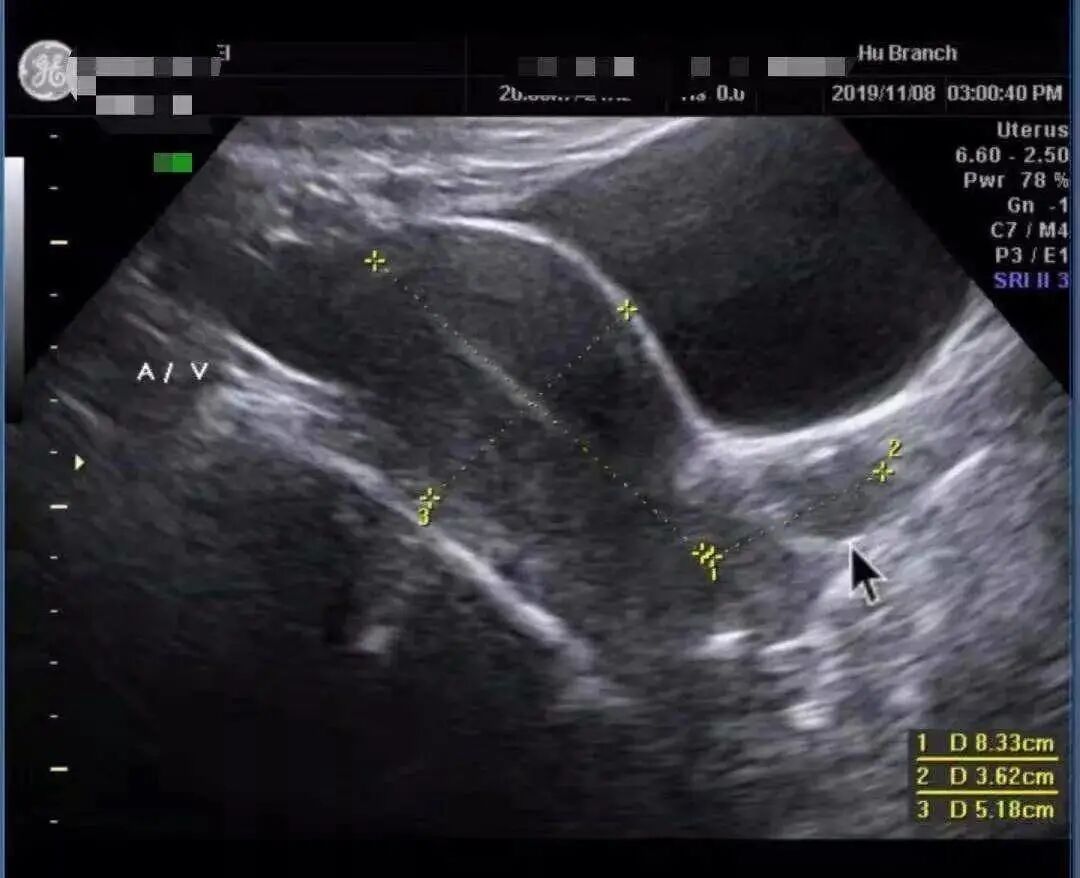

医生给她查了B超,怀疑有子宫肌瘤卡在宫颈上。

经过宫腔镜检查,确诊为子宫肌瘤卡在宫颈。

张教授建议病人,可以在麻醉下接受经阴道切除肌瘤。因为病人有不规则的出血,并不能排除她有子宫内膜癌的可能,需要诊断性刮宫。